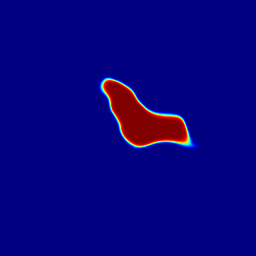

Finally, Fig. 9 displays examples of output probability maps from all of the comparative methods, i.e., HNN [12], UNet [16], PNet-MSA and “PNet-MSA+BiRNN”, where the latter one delivers the sharpest and clearest output on both CT and MRI datasets. More specifically, PNet-MSA presents results that are detailed and recover the major part of the pancreas, where both HNN and UNet suffer from significant low segmentation recall. When observing the BiRNN outputs for CT and MRI, we find detailed pancreas parts in CT have been recovered via shape continuity learning and regularization, while in MRI, the BiRNN only outputs probability map with the same shape in PNet-MSA’s output, which is optimal when the inter-slice shape changes drastically in the MRI dataset. Thus, BiRNN would help to refine pancreas segmentation with a smoothed surface in the situation that slice thickness of the 3D scans is reasonably small, e.g., <2absent2<2mm.

Figure 9: Examples of output probability map: columns from left to right are the input CT/MRI image, results from HNN [12], UNET [16], the proposed PNet-MSA sub-network, and the full CNN-RNN (“PNet-MSA+BiRNN”), and the ground truth. Our model delivers the most clear probability maps which preserve detailed pancreatic boundaries.